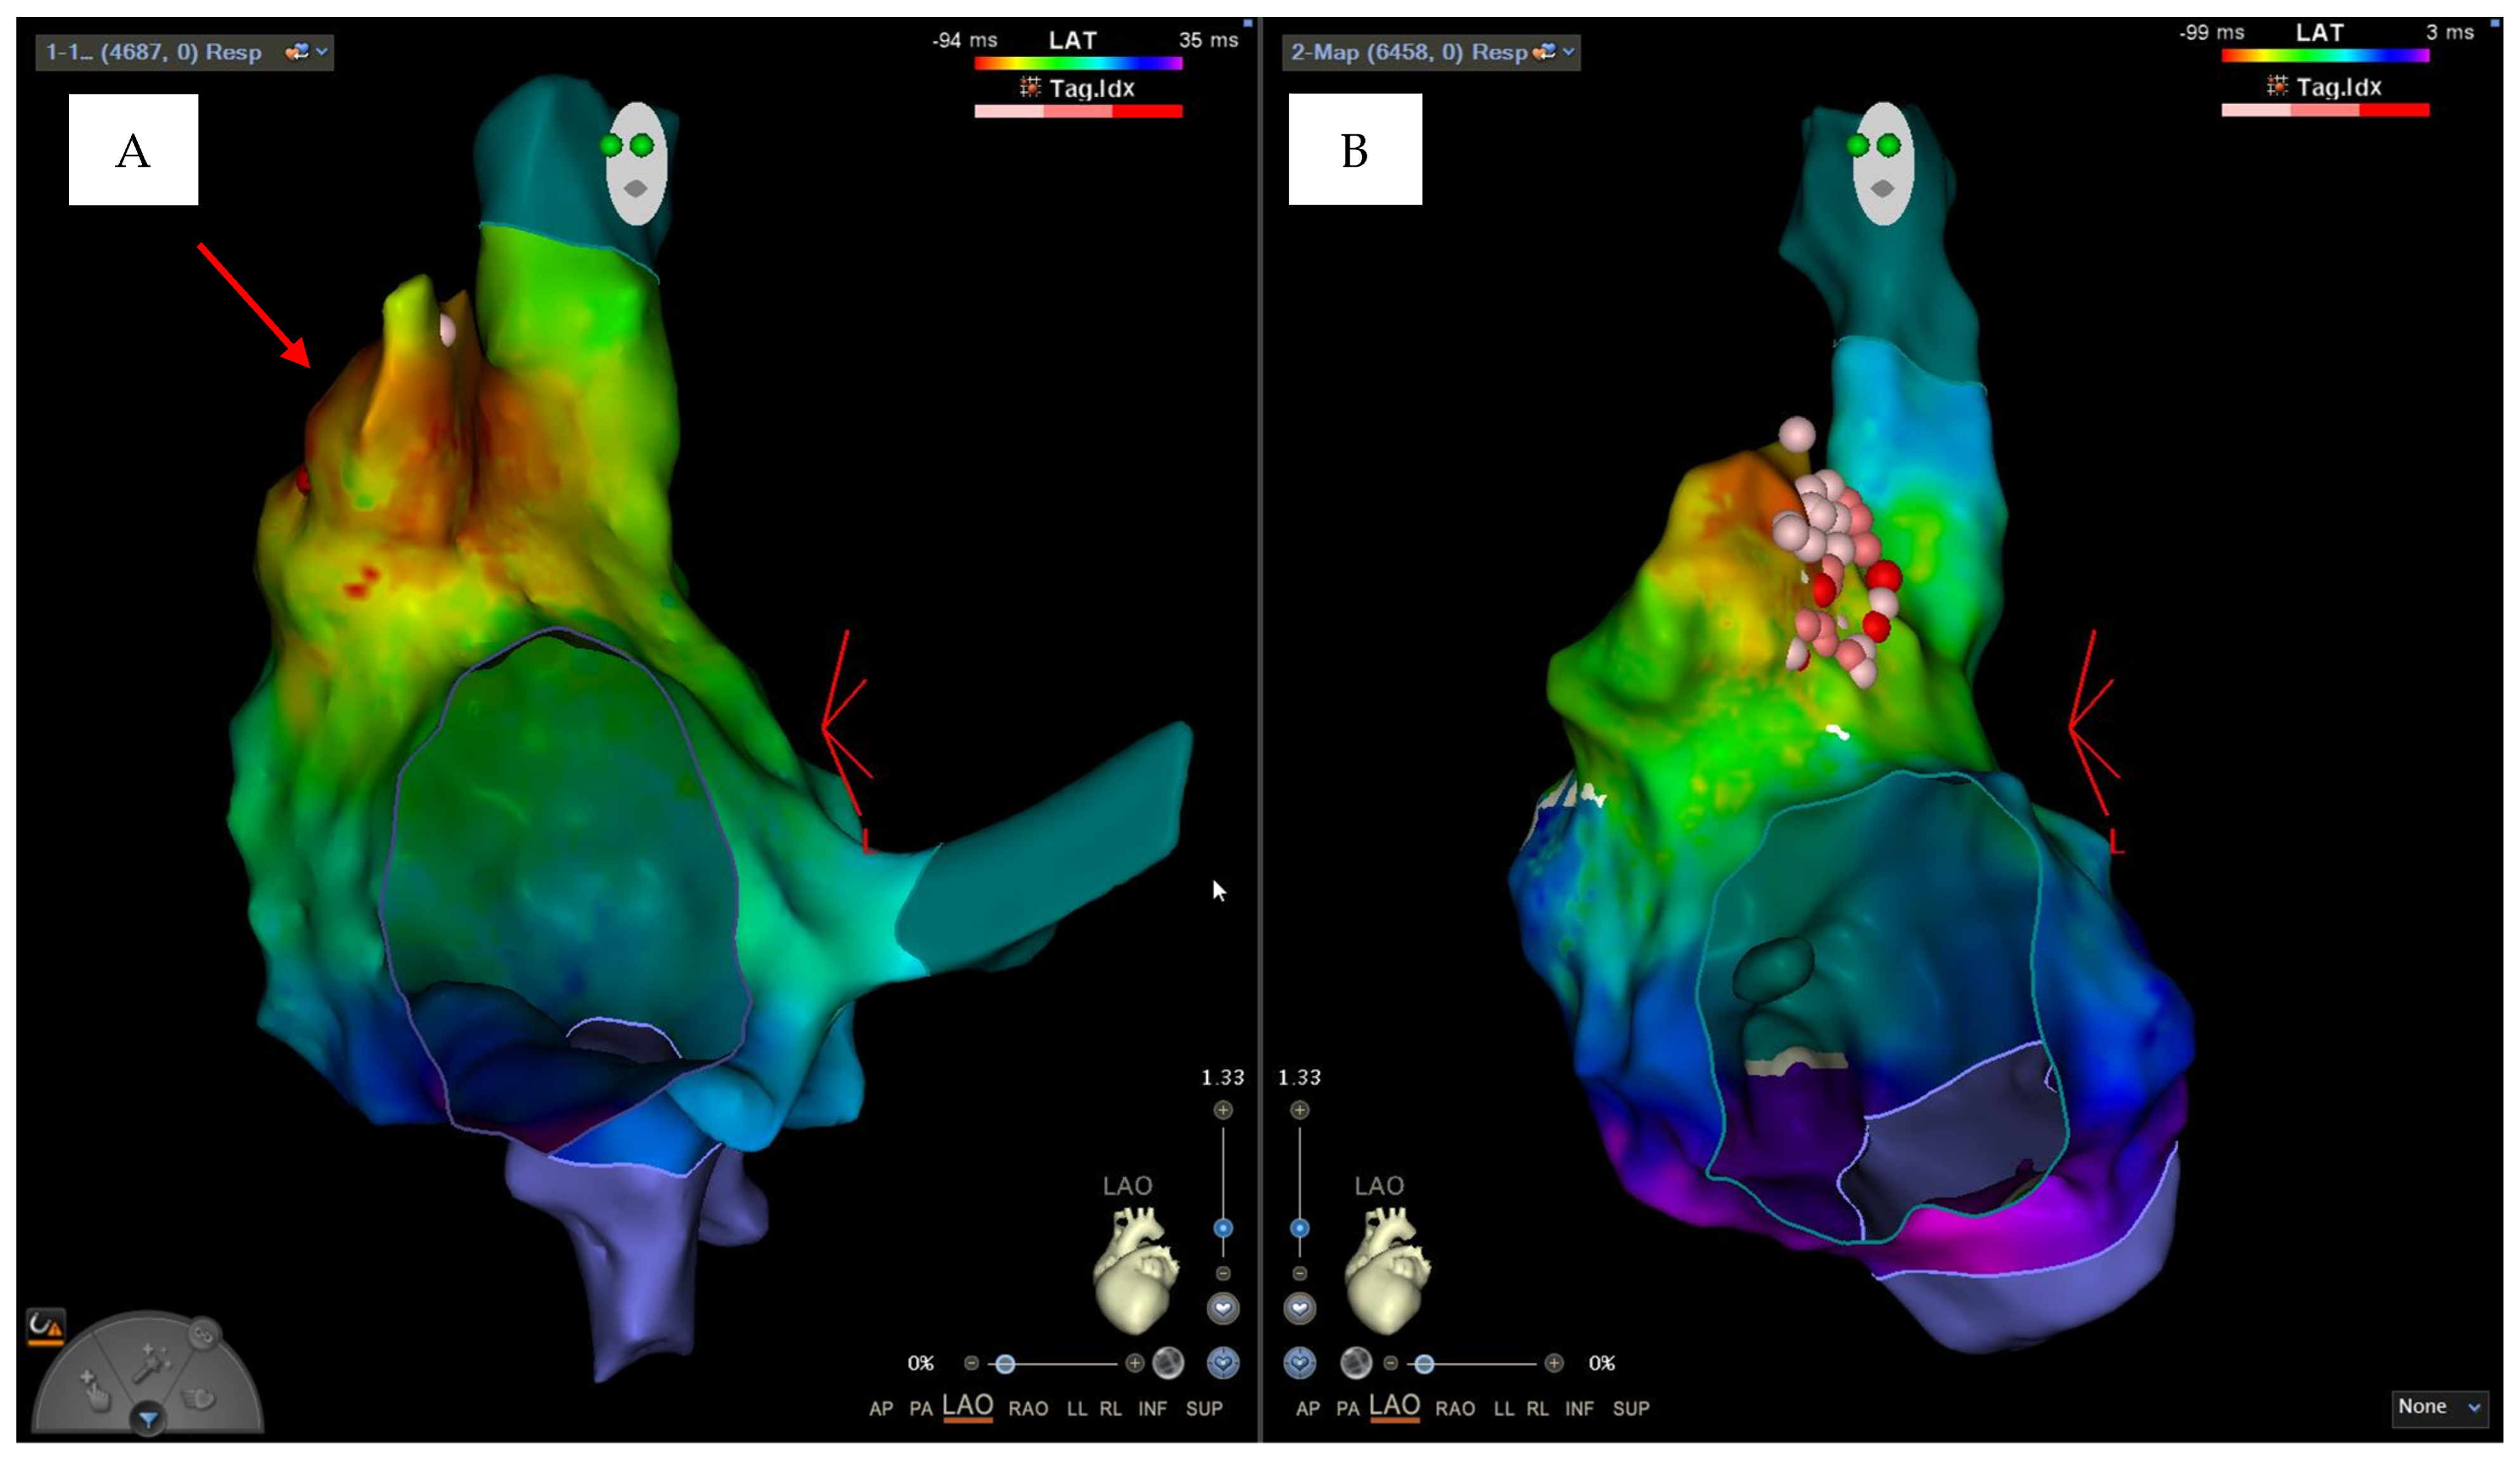

2. Case Description